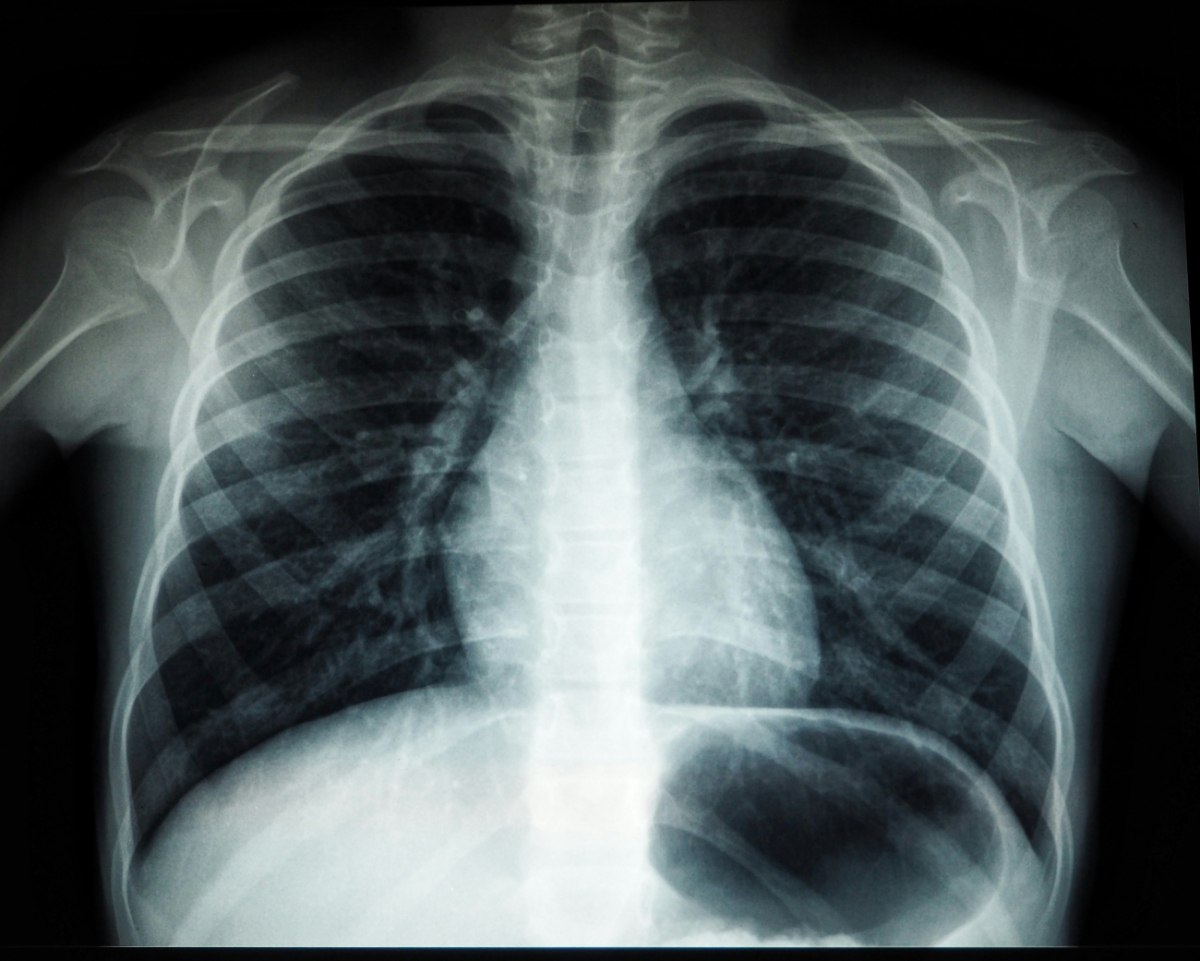

Η ατμοσφαιρική ρύπανση συνδέεται με μεταλλάξεις του DNA που προκαλούν καρκίνο του πνεύμονα

Ο καρκίνος του πνεύμονα παραδοσιακά συνδέεται με το κάπνισμα, όμως τα τελευταία χρόνια παρατηρείται αύξηση στα περιστατικά μεταξύ μη καπνιστών

Μια πρόσφατη μελέτη έδειξε ότι η ατμοσφαιρική ρύπανση συνδέεται με μεταλλάξεις στο DNA που ευθύνονται για την ανάπτυξη καρκίνου του πνεύμονα.

Η έρευνα αναδεικνύει πως όσο υψηλότερα είναι τα επίπεδα ρύπανσης σε μια περιοχή, τόσο αυξάνεται ο αριθμός μεταλλάξεων που προάγουν την εμφάνιση της νόσου, ακόμα και σε άτομα που δεν έχουν καπνίσει ποτέ.